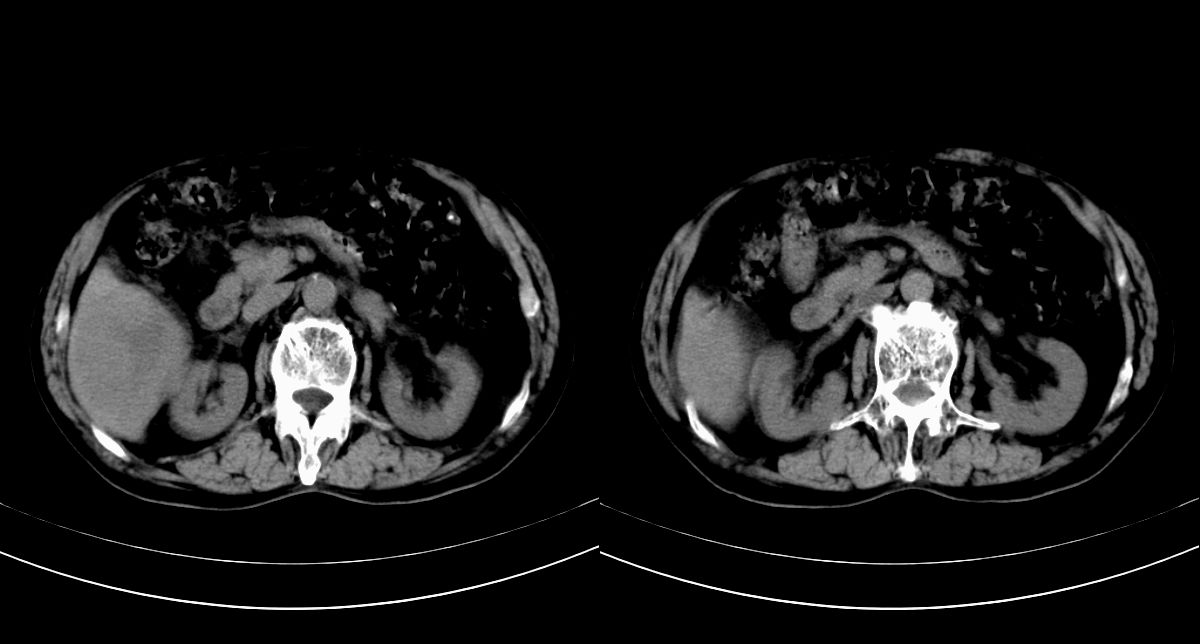

男,79y,无不适。体检发现肝脏占位。

肝内多发低密度结节,增强动脉期明显强化,门脉期逐渐下降,内有液化坏死区。

肝内多发低密度结节灶,增强动脉期明显不规则环状强化,;门脉期逐渐下降,肿瘤壁厚薄不一,内有坏死液化区。

诊断:肝转移癌可能

支持多发结节巨块型肝癌,建议查afp。

巨块型肝癌伴肝内转移.

肝内转移瘤,查原发灶吧。

诊断:典型的肝转移癌